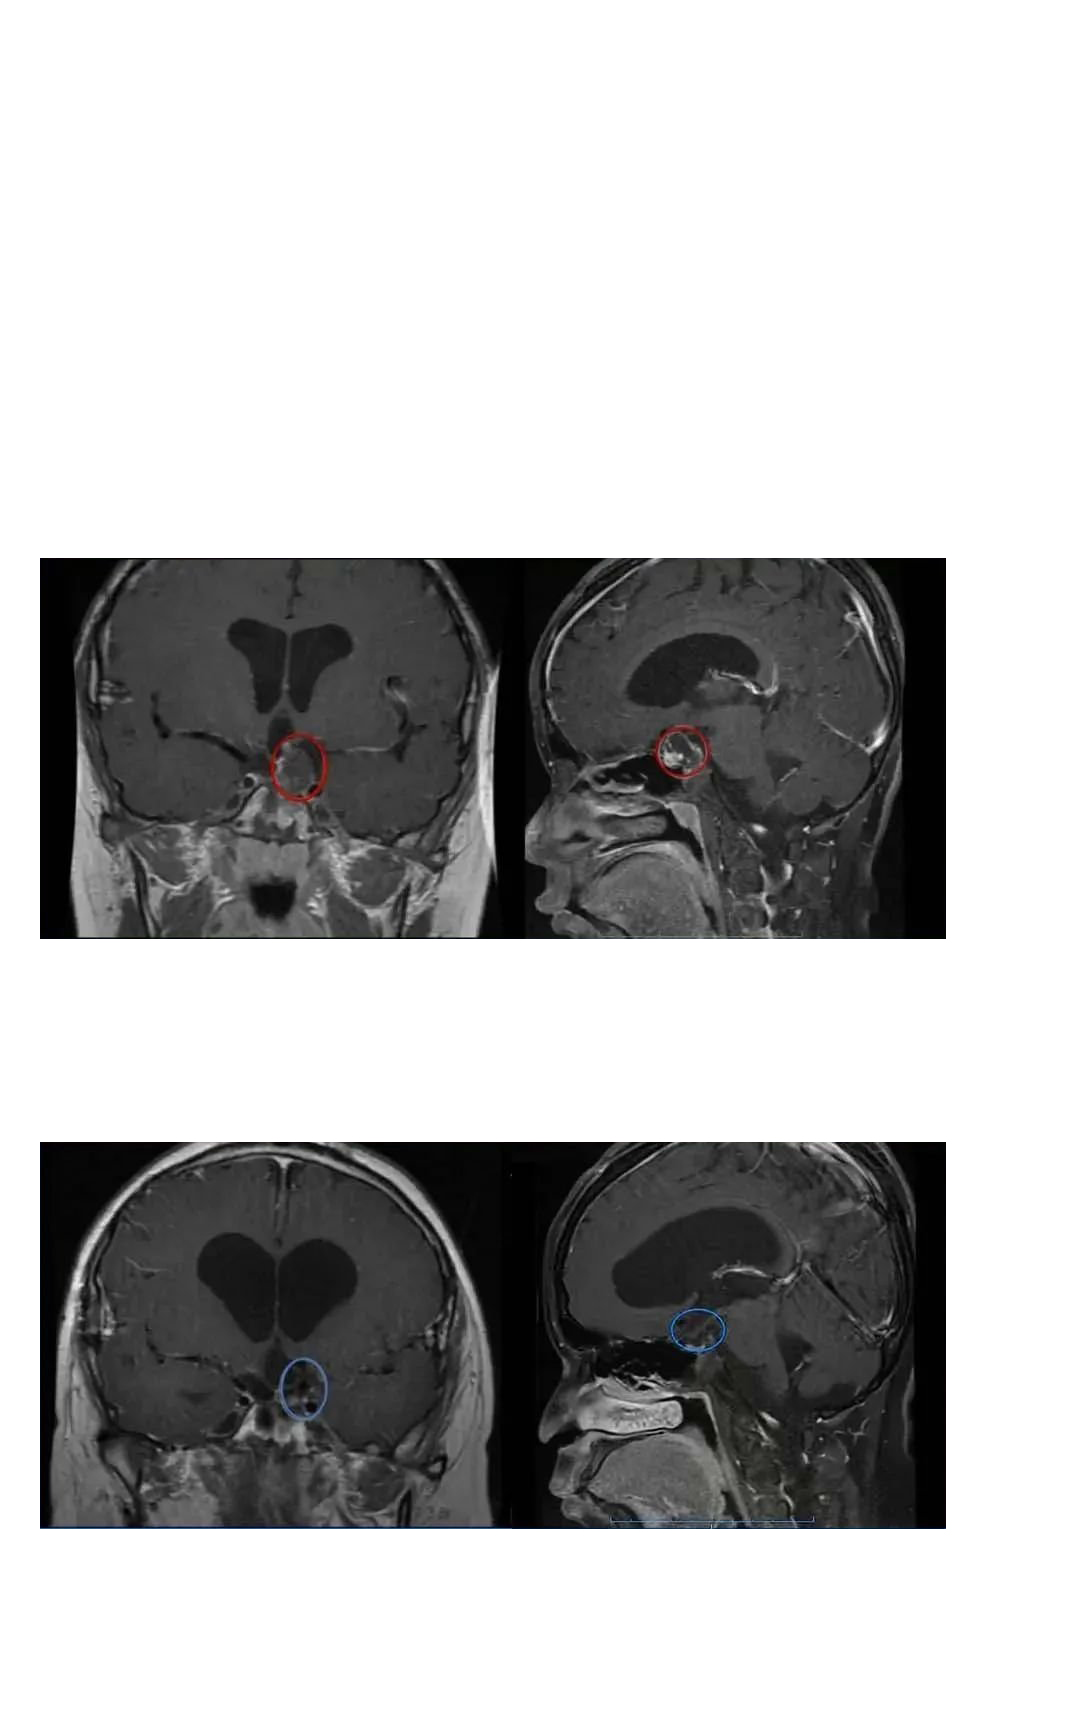

简要病史:80岁的李奶奶,2023年初开始出现短暂视物模糊以及记忆力减退等症状,在老伴的陪同下去医院检查发现:鞍上区占位性病变,颅咽管瘤可能性大。眼科检查后,确实双侧视野同侧缺损(左侧),视物模糊,可能是脑子里的这颗肿瘤造成的。

术前症状:双侧视野同侧缺损(左侧),视物模糊。

远程咨询巴教授后。巴教授表示,开颅手术中无需切除垂体柄,肿瘤切除率也会达到98-99%,手术风险低,而且视野和视物模糊在开颅术后的几周内可以得到完全恢复。为了得到更好的治疗,他们决定选择巴教授手术。

手术记录:2023年3月25日,在苏州独墅湖医院,INC巴教授顺利为李奶奶顺利全切手术。

李奶奶的术前术后MRI对比,红色为术前肿瘤位置,绿色为术后切除效果

术后情况:术后一天ICU查房李奶奶和巴教授愉快交流,复视较术前好转。术后四天普通病房查房李奶奶复视完全好转,状态很好,可以坐起来。术后两周李奶奶恢复良好顺利出院。

术后两个月李奶奶恢复正常生活,李奶奶还特意寄来了感谢巴教授和INC的定制礼物。